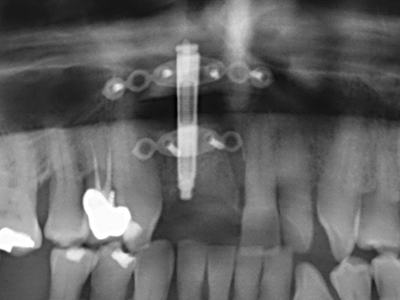

Фиг. 15: Прегледът на рентгеновата снимка след 1 година показва стабилно състояние на нивото на костта.

Фиг. 13: Подходяща иригация с остатъчна 4 mm дебелина на костта е важна за този 52-годишен пациент по време на разделянето на костта.

Фиг. 14: Поставяне на RSX имапланта (Bego Implant Systems, Bremen).